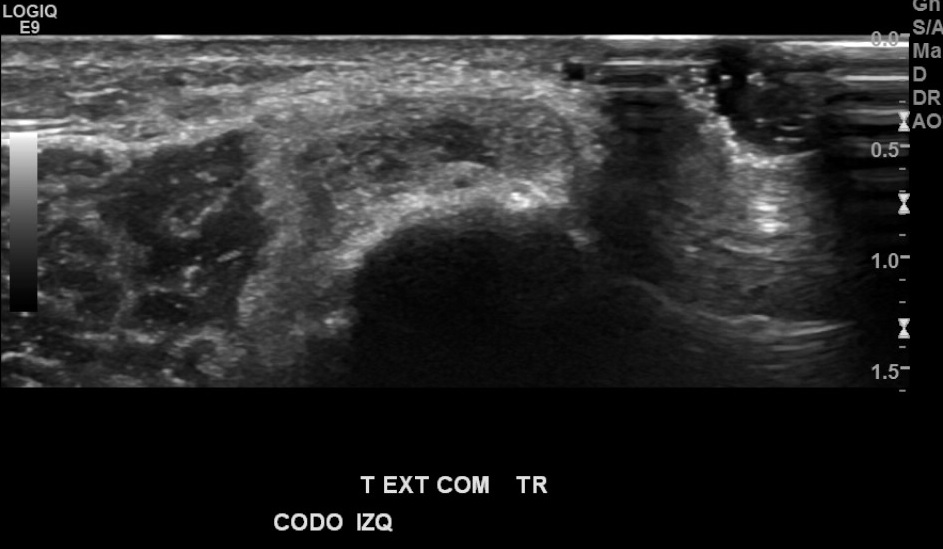

Antecedentes: chequeo por marcado dolor de región epicondilo lateral de codo izquierdo, mayor hace 1 mes aprox., por esfuerzo laboral de EESS, sin trauma.

Hallazgos: marcada heterogeneidad de tendón extensor común izquierdo, con foco de desgarro de espesor y ancho parcial en su espesor, con hiperemia al doppler color.